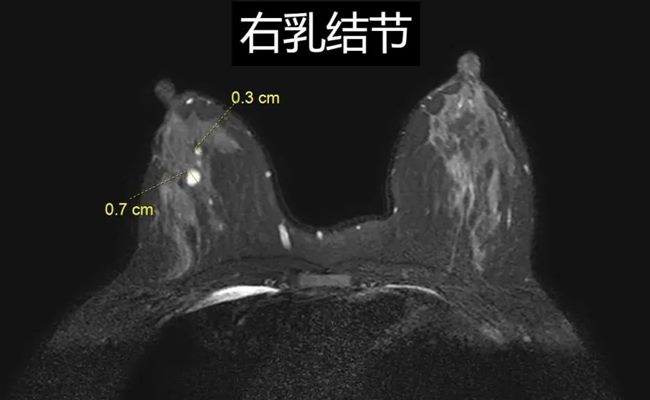

它的侦查能力堪称一绝,哪怕是< 5 毫米的恶性病灶也无处遁形,敏感性高达 90% 以上!在癌症还处于萌芽阶段时,就能及时拉响警报,为治疗争取宝贵时间。

无论是化疗还是手术后,乳腺磁共振都能精准评估肿瘤是否缩小或复发,时刻关注病情变化,是医生制定治疗方案的得力助手。